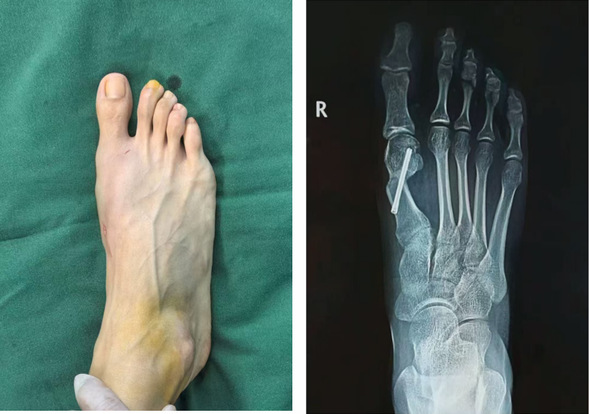

第三代拇外翻微创术前

这三位患者均为足拇趾外翻多年,随着年龄增长,外翻的程度越来越严重,穿鞋困难、疼痛难忍,已严重影响到日常生活,于是来到我院骨外四科就诊。在骨外科主任邢星的带领下,经过术前病情分析和讨论,周密检查,决定行微创拇外翻技术治疗。在麻醉科与手术室的密切配合下,顺利完成手术。术中仅1个不足1 厘米小切口,患者患足术后外观恢复满意。拇外翻(俗称“大脚骨”),总体发病率为10%—20%,女性占比远高于男性。

拇外翻角(HVA)大于15°,跖间角(IMS)大于10°,结合临床表现就可以判断拇外翻,生活质量下降。传统拇外翻手术往往需要较大的切口和复杂的内固定操作,术后恢复周期长且伴有一定的痛苦,邢星主任团队所采用的第三代拇外翻矫治技术,则以其微创特点,改变了这一现状,患者在接受手术后,足部畸形得到即时纠正,外观更加美观自然,避免了二次手术取内固定的繁琐与痛苦。目前第三代拇外翻微创手术已得到国际足踝外科学会(IFFAS)、美国足踝外科学会(AOFAS)等权威机构认证。